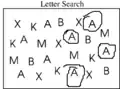

Some of the neglect tests.

Letter search neglect test

Letter search neglect test Letter search neglect test result

Letter search neglect test result Line cancellation neglect test

In order to assess not only the type but also the severity of neglect, doctors employ a variety of tests, most of which are carried out at the patient's bedside. Perhaps one of the most-used and quickest is the line bisection. In this test, a line a few inches long is drawn on a piece of paper and the patient is then asked to dissect the line at the midpoint. Patients exhibiting, for example, left-sided neglect will exhibit a rightward deviation of the line's true midpoint.[6]

Another widely used test is the line cancellation test. Here, a patient is presented with a piece of paper that has various lines scattered across it and is asked to mark each of the lines. Patients who exhibit left-sided neglect will completely ignore all lines on the left side of the paper.[6]

Visual neglect can also be assessed by having the patient draw a copy of a picture with which they are presented. If the patient is asked to draw a complex picture they may neglect the entire contralesional side of the picture. If asked to draw an individual object, the patient will not draw the contralesional side of that object.[14]

A patient may also be asked to read a page out of a book. The patient will be unable to orient their eyes to the left margin and will begin reading the page from the center. Presenting a single word to a patient will result in the patient either reading only the ipsilesional part of the word or replacing the part they cannot see with a logical substitute. For example, if they are presented with the word "peanut", they may read "nut" or say "walnut".[14]